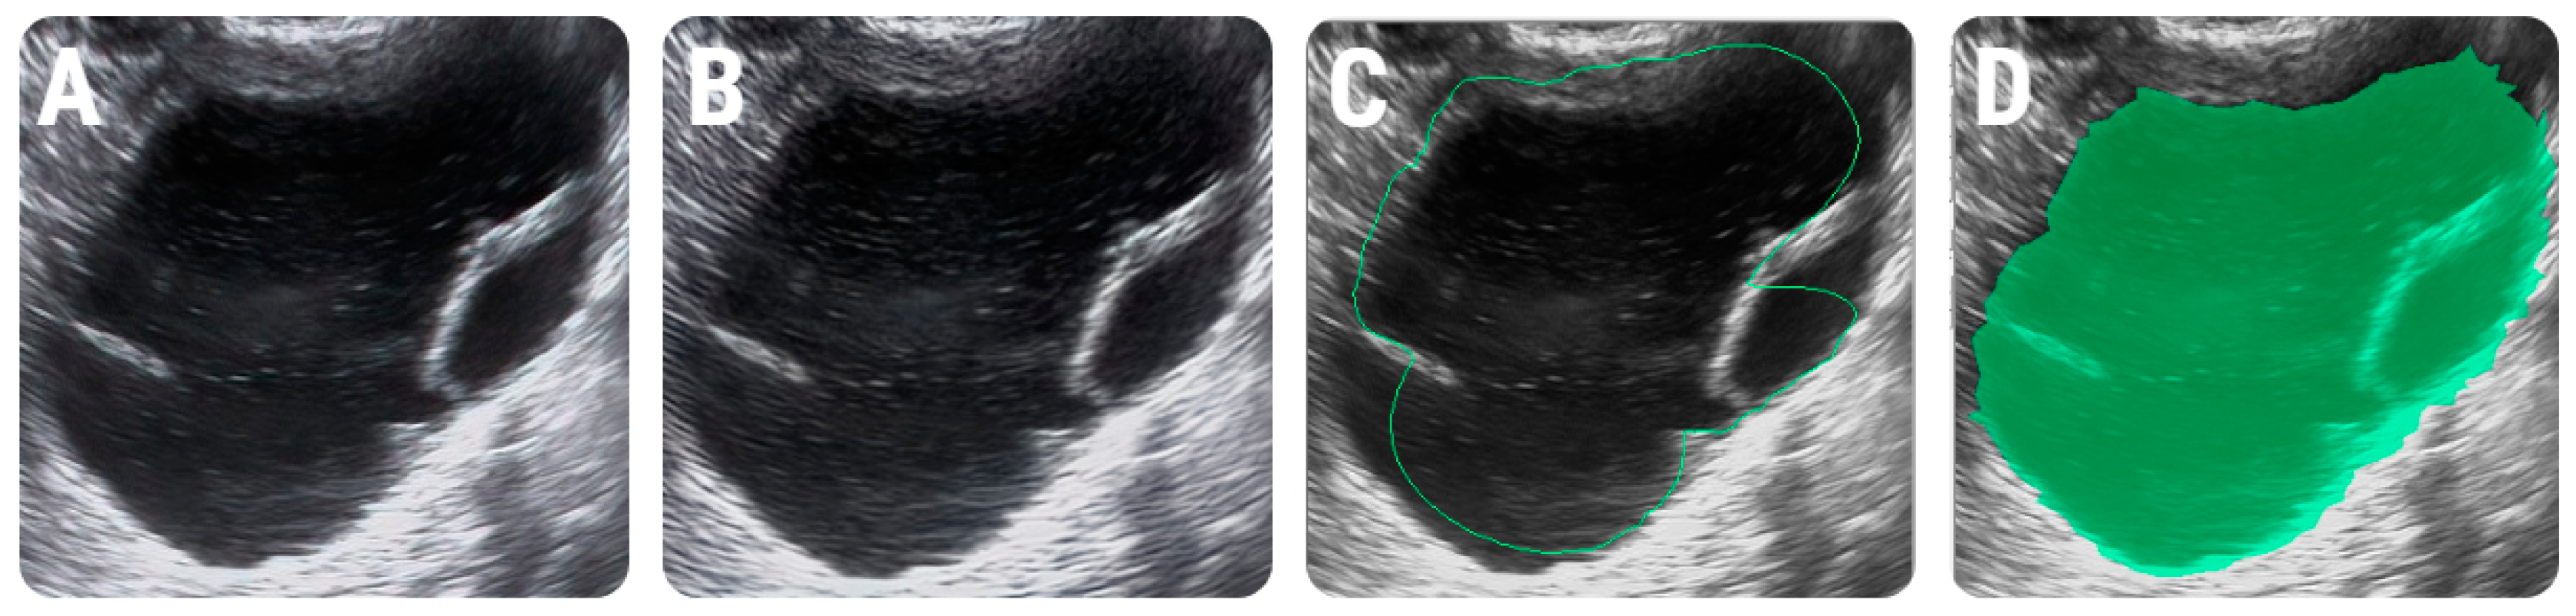

2.4.1. Image Pre-Processing and Segmentation